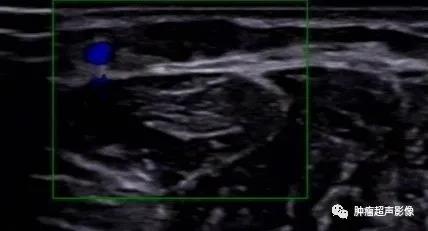

超声表现:一般呈低回声(少部分为高回声,胃血管球瘤一般都呈高回声,类似肝脏血管瘤表现),多为类圆形或椭圆形,边界清,较大肿瘤可显示其对指骨的侵蚀,内部及周边血流丰富,典型的呈花环状或小火球样,频谱呈低速低阻。

病理证实的血管球瘤,右前臂压痛,超声显示皮下低回声,边界清,类圆形,无血流,诊断比较困难。